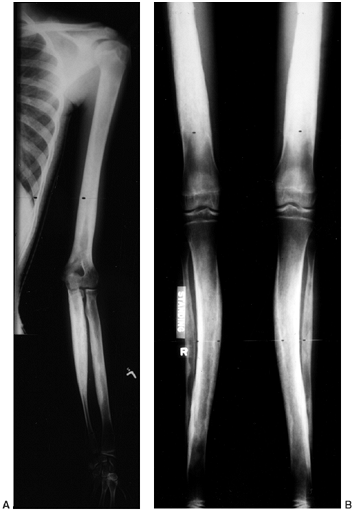

![]() |

Figure 10.2 A:

A 15-year-old boy with Klippel-Trenaunay syndrome of his right lower extremities with typical findings of hypertrophy, varicosities, and superficial complex, combined vascular malformations. B, C: He had aching discomfort from the varicosities, intermittent pain from thrombophlebitis, and drainage from the superficial vascular malformations. |

than the upper extremities. The affected limb is longer than normal in 90% of the patients (16,37,46). Usually, all bones and soft tissues in the limb are involved in the hypertrophy (Fig. 10.2).